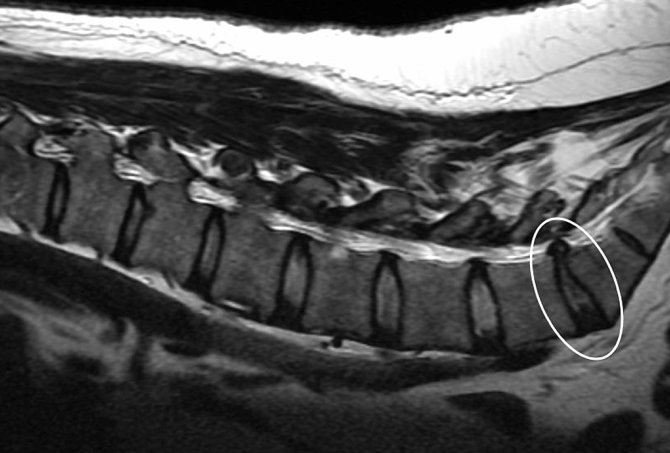

4 stupnja diskus hernije (Koliko je situacija ozbiljna)

Protruzija ili hernijacija diska označava njegovo oštećenje, degenerativnu promjenu u strukturi koja se događa, prirodno, u procesu starenja ili uslijed vanjskog oštećenja. Saznajte sve o problemu koji sve češće zahvaća i mlađu populaciju.